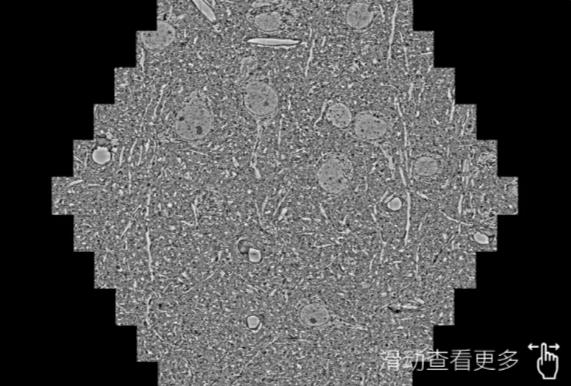

鼠脑切片。左图使用石景山蔡司石景山扫描电镜MultiSEM706对165μmx143pm面积区域成像,耗时仅需1.5秒。右图为鼠脑切片中30μm区域放大效果。样品由芝加哥大学B.Kasthuri提供。

使用蔡司高速石景山扫描电镜MultiSEM对1mm²人脑皮层组织进行高分辨成像,并对其中的各种细胞结构进行三维重构分析。左图展示了2x3mm²组织平面中锥体神经元的三维重构效果。右图显示了局部体积神经元三维重构。图像由哈佛大学chtman实验室提供,渲染图由D. Berger 制作。